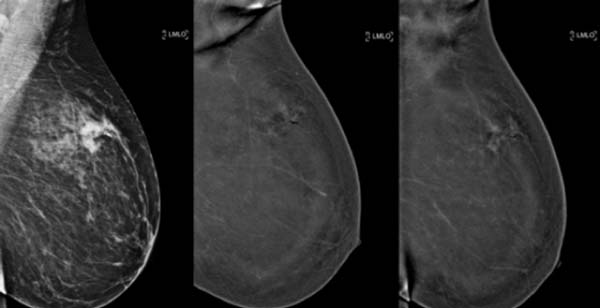

La ricerca tecnologica ha perciò cercato di sopperire a tali limiti della mammografia digitale sviluppando la MAMMOGRAFIA CON TOMOSINTESI.

Si tratta, in pratica di una Mammografia Tridimensionale (3D) ad Alta Definizione.

La TOMOSINTESI è una procedura diagnostica che permette di studiare la mammella ‘a strati’, come la TC; la mammella viene scomposta in tante immagini che poi, sovrapposte, ricostruiscono la figura della mammella nella sua completezza.